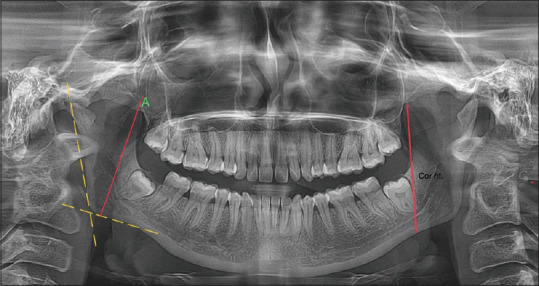

Materials and methods: A total of 200 digital panoramic radiographs were collected, out of which 100 were males and 100 were females. The average age range of the samples was 20-40 years. Coronoid height and condylar height were measured using Planmeca Romexis Viewer Software version 2.9.2.R (Planmeca OY, Helsinki, Finland). Random forest and elastic net algorithms were employed in the study.